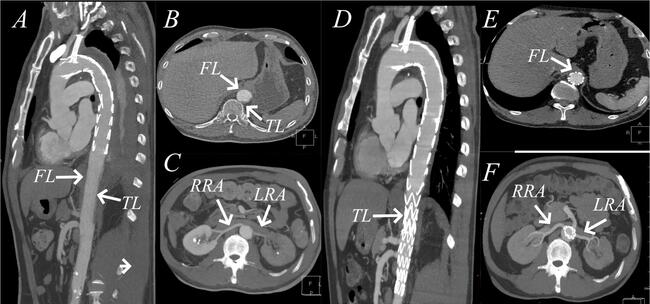

Emergency computed tomography angiography (CTA) showed that the distal segment of the stent graft had been deployed into the false lumen (FL), leading to complete collapse of the TL and the left renal artery (Figure A-C). Angiography confirmed the CT findings (Video 1).

The patient underwent immediate thoracic endovascular aortic repair. The balloon dilated the true cavity at the end of the stent to rupture the intima and enable communication between the true and false cavities; the bare and covered stents were respectively introduced through the rupture (Video 2). The operation was successful, and the patient recovered well and was discharged 4 days later. Two months postoperative, CTA reexamination showed complete absorption of the FL (Figure D-F). The glomerular filtration rate was 53 mL/min.